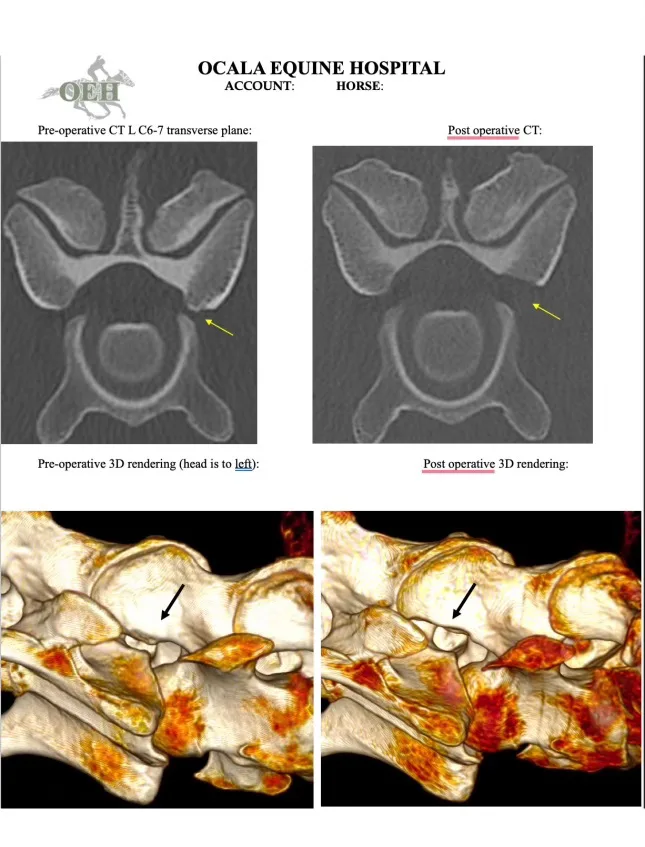

Kozumplik turned to Jonathan Furlong, DVM, MSEd, of B.W. Furlong and Associates in Oldwick, New Jersey, for advice. Initially, they wondered if Rocky’s back was bothering him, but Furlong couldn’t isolate a problem; a lameness exam turned up nothing unusual. Ultimately, Furlong took several standing cervical radiographs and determined Rocky might have an area of compression between the C6 and C7 vertebrae in his neck. But overall, nothing definitive emerged, and with the support of her veterinary team, Kozumplik continued pursuing her training and competitive goals.

“We are so lucky in this sport to have a lot of good relationships, and they are both really good at this type of thing, to determine if a problem is veterinary or technical,” Kozumplik said. “And Lynn said to me, ‘He is really pushing into your left leg.’ She could see that in the video—and told me I should do a [computed tomography] scan of his neck.”

The week after Carolina, Furlong referred Rocky to the team at Ocala Equine Hospital, where Travis Tull, DVM, DACVS, consulted. After Rocky’s CT scan—which gives a comprehensive 3-D view—Tull confirmed Furlong’s initial suspicion. Rocky was indeed experiencing compression in one area where his spinal nerves exit the spinal column, resulting in cervical radiculopathy. In layman’s terms, Rocky had a pinched nerve in his neck that was likely causing pain and interfering with the mobility of his left foreleg.

“The most common cause in horses is an enlarged articular process joint, which are paired joints between the vertebrae on either side of the spinal canal,” Tull explained. “The enlargement can cause a narrowing of the opening where the cervical spinal nerve travels to relay information to and from the spinal cord.”